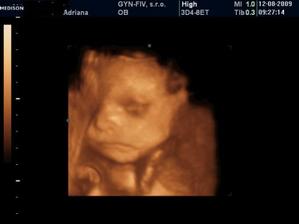

3.6. Uzasny 3D ultrazvuk...Videli sme nasho mimiska... Meriame bez noziciek 10 cm a s nozickami skoro 15 cm... 🙂 A doktor nas prekvapill, ze vraj to bude chlapcek... 🙂 14.7. morfologicky ultrazvuk, vsetko zatial vyzera v poriadku - tesime sa na Andrejka 🙂 12.8. 3D ultrazvuk - ma to 35 cm a 900 gramov, kto je to? No predsa ja Andrejko... 🙂